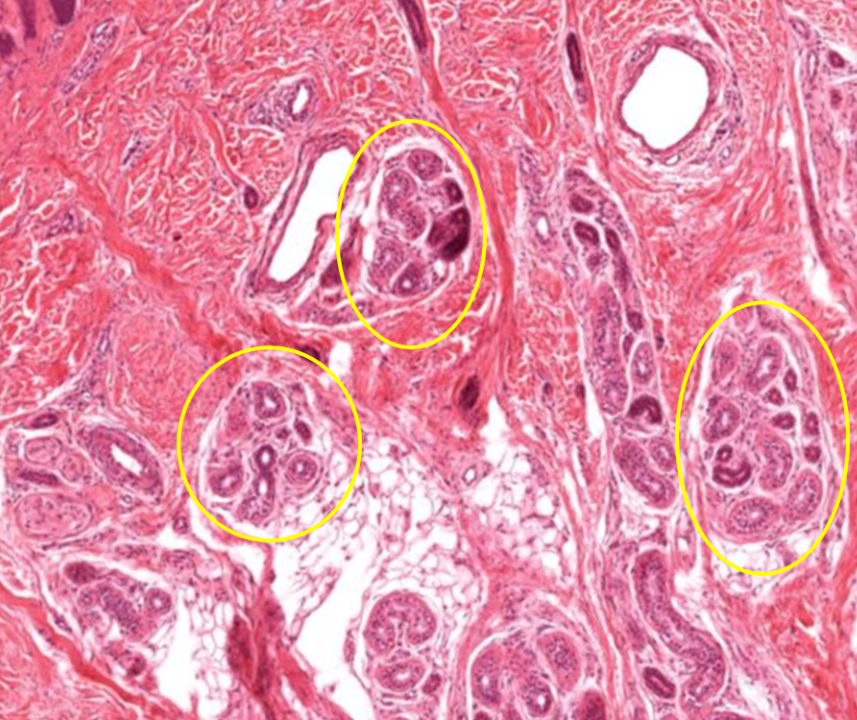

Concreções prostéticas

Próstata